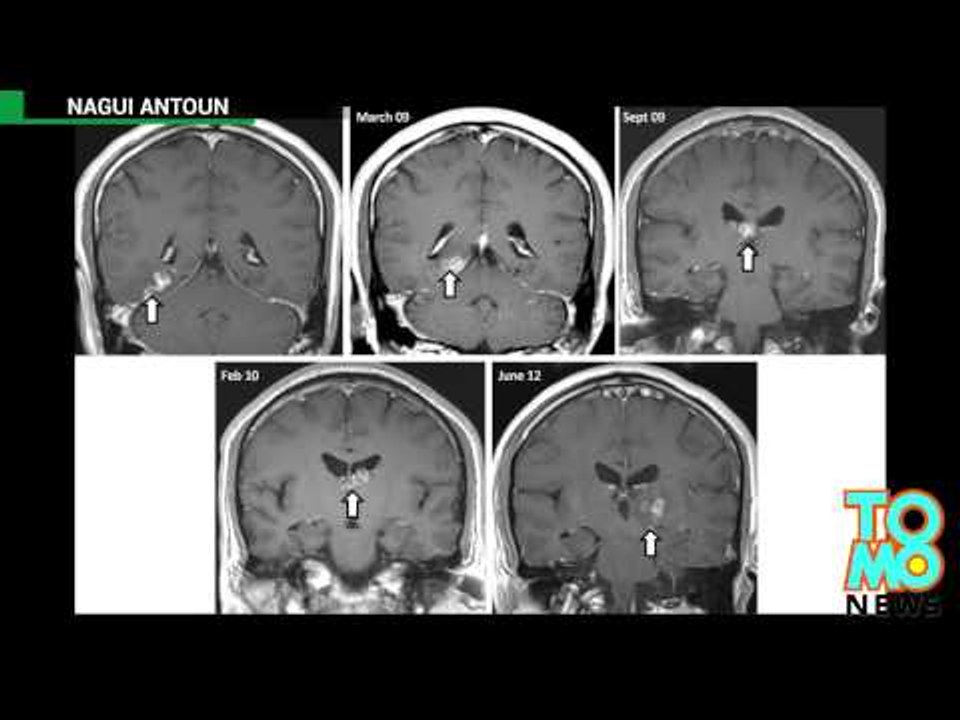

Pasożyt przez 4 lata przegryzał się przez mózg mężczyzny 1:17

Pasożyt przez 4 lata przegryzał się przez mózg mężczyzn...

TomoNews PL 135 views